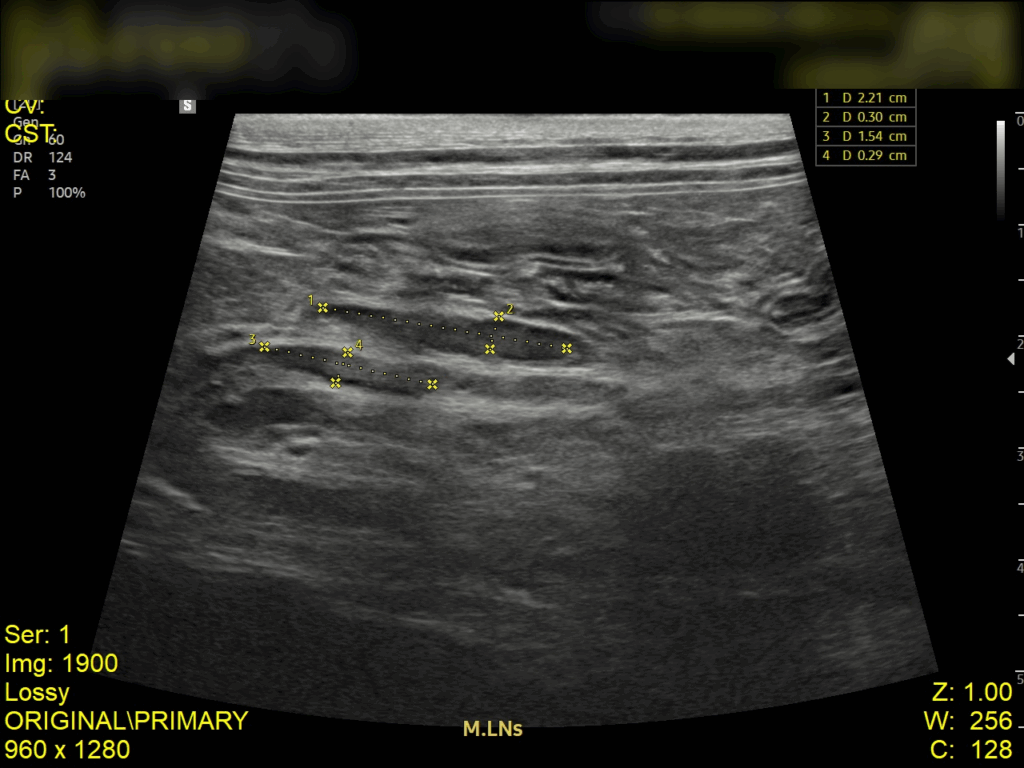

복부 초음파 검사 결과

초음파 검사 결과, 복강 내 림프절이 비대된 모습이 확인되었고, 장벽 두께가 정상보다 두꺼워진 것을 확인되었습니다. 이는 장 내 염증 반응이나 감염성 원인에 의해 장벽이 자극을 받고 있음을 의미합니다.